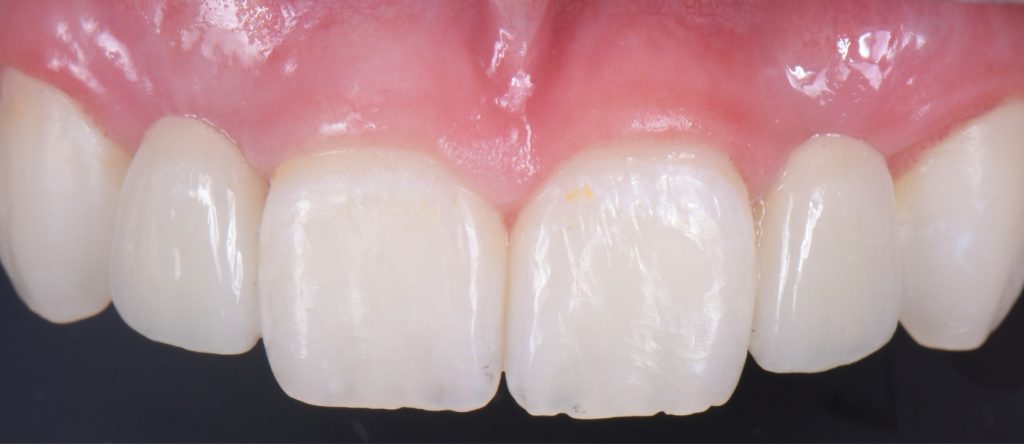

Solution #2: Resin-Bonded Fixed Dental Prostheses (RBFDP)

RBFDP is a proven solution for congenitally missing lateral incisors (Figs. 2-12). Although it is considered an interim restoration, the literature provides substantial evidence supporting its long-term potential. However, the clinical performance of an RBFDP is significantly superior to that of a bilateral retainer, and the dissimilar mobility of the abutment teeth explains this.

Space requirements and connector dimensions depend on material selection. Utilizing zirconia has been proven to be more predictable over time, and recommended connector dimensions are:

The amount of tooth reduction is based on available interocclusal space, and often, there is enough space requiring minimal preparation. The key is to stay in enamel. It is also advisable to stay 2.0 mm away from the incisal edge so that the zirconia retainer does not affect the translucency of the natural tooth.

RBFPD has an exceptional record, so this cantilever bridge can be considered a long-term solution. However, if in the future an implant-supported restoration is desired, the pontic of this cantilever can be removed, and an implant could be placed and restored.